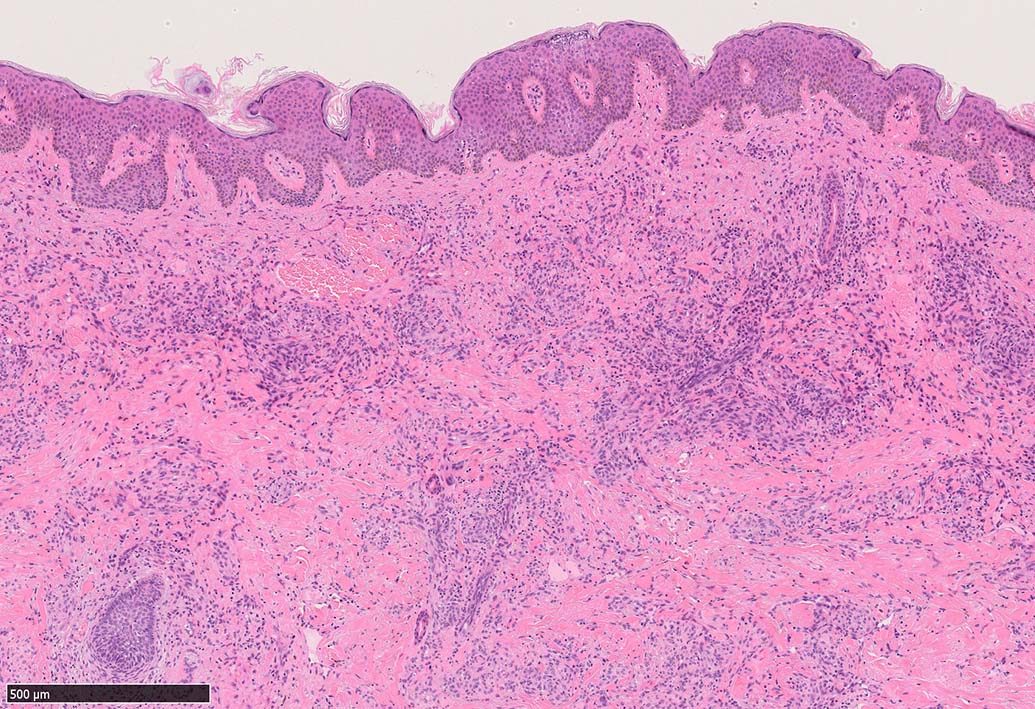

局面状病変の病理

病変は真皮から皮下脂肪織に及ぶようになり, 血管内皮様細胞による新生管腔の増加と拡張, 浮腫が著明になる. 赤血球漏出やヘモジデリン貪食細胞もめだつようになる.

膠原線維間に紡錘形細胞が増生してくる.

細血管周囲に血管内皮様の紡錘形細胞が増生, 一部に赤血球をいれた裂隙の形成がある. 細胞の異型はみられず, mitosisの増多もない. hemosiderin-laden macrophageが散在する.

病変は真皮内に現局している. 初期斑状病変に相当すると考えられる. 本例では, 特徴とされる形質細胞浸潤増加はみられない.